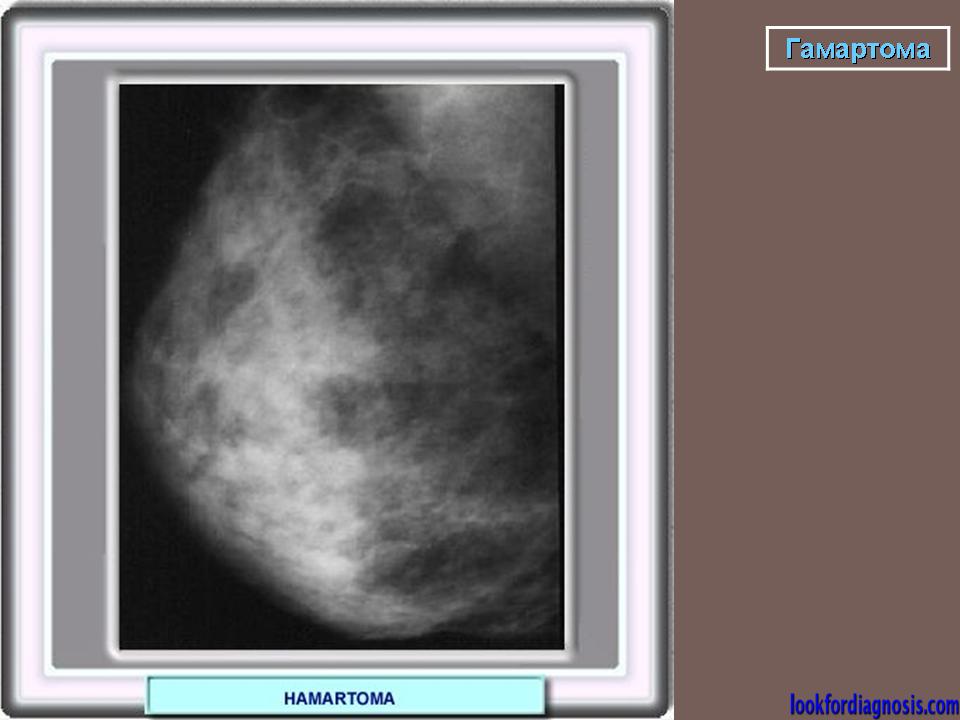

Гамартома.